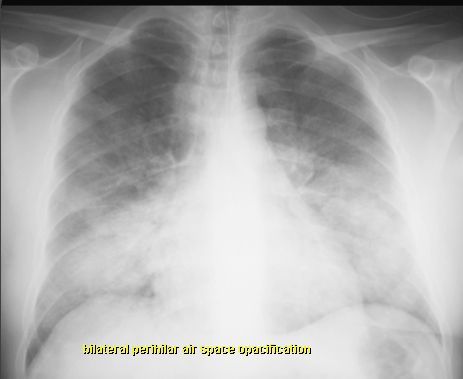

OBRZĘK PŁUC

RTG